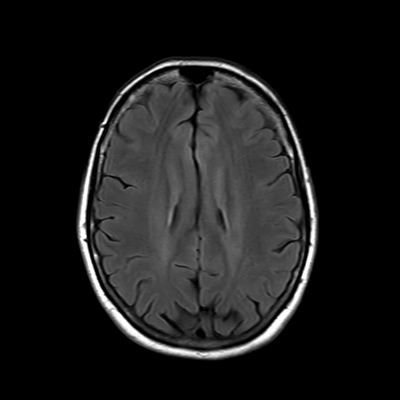

MRI brain (FLAIR)

4/18